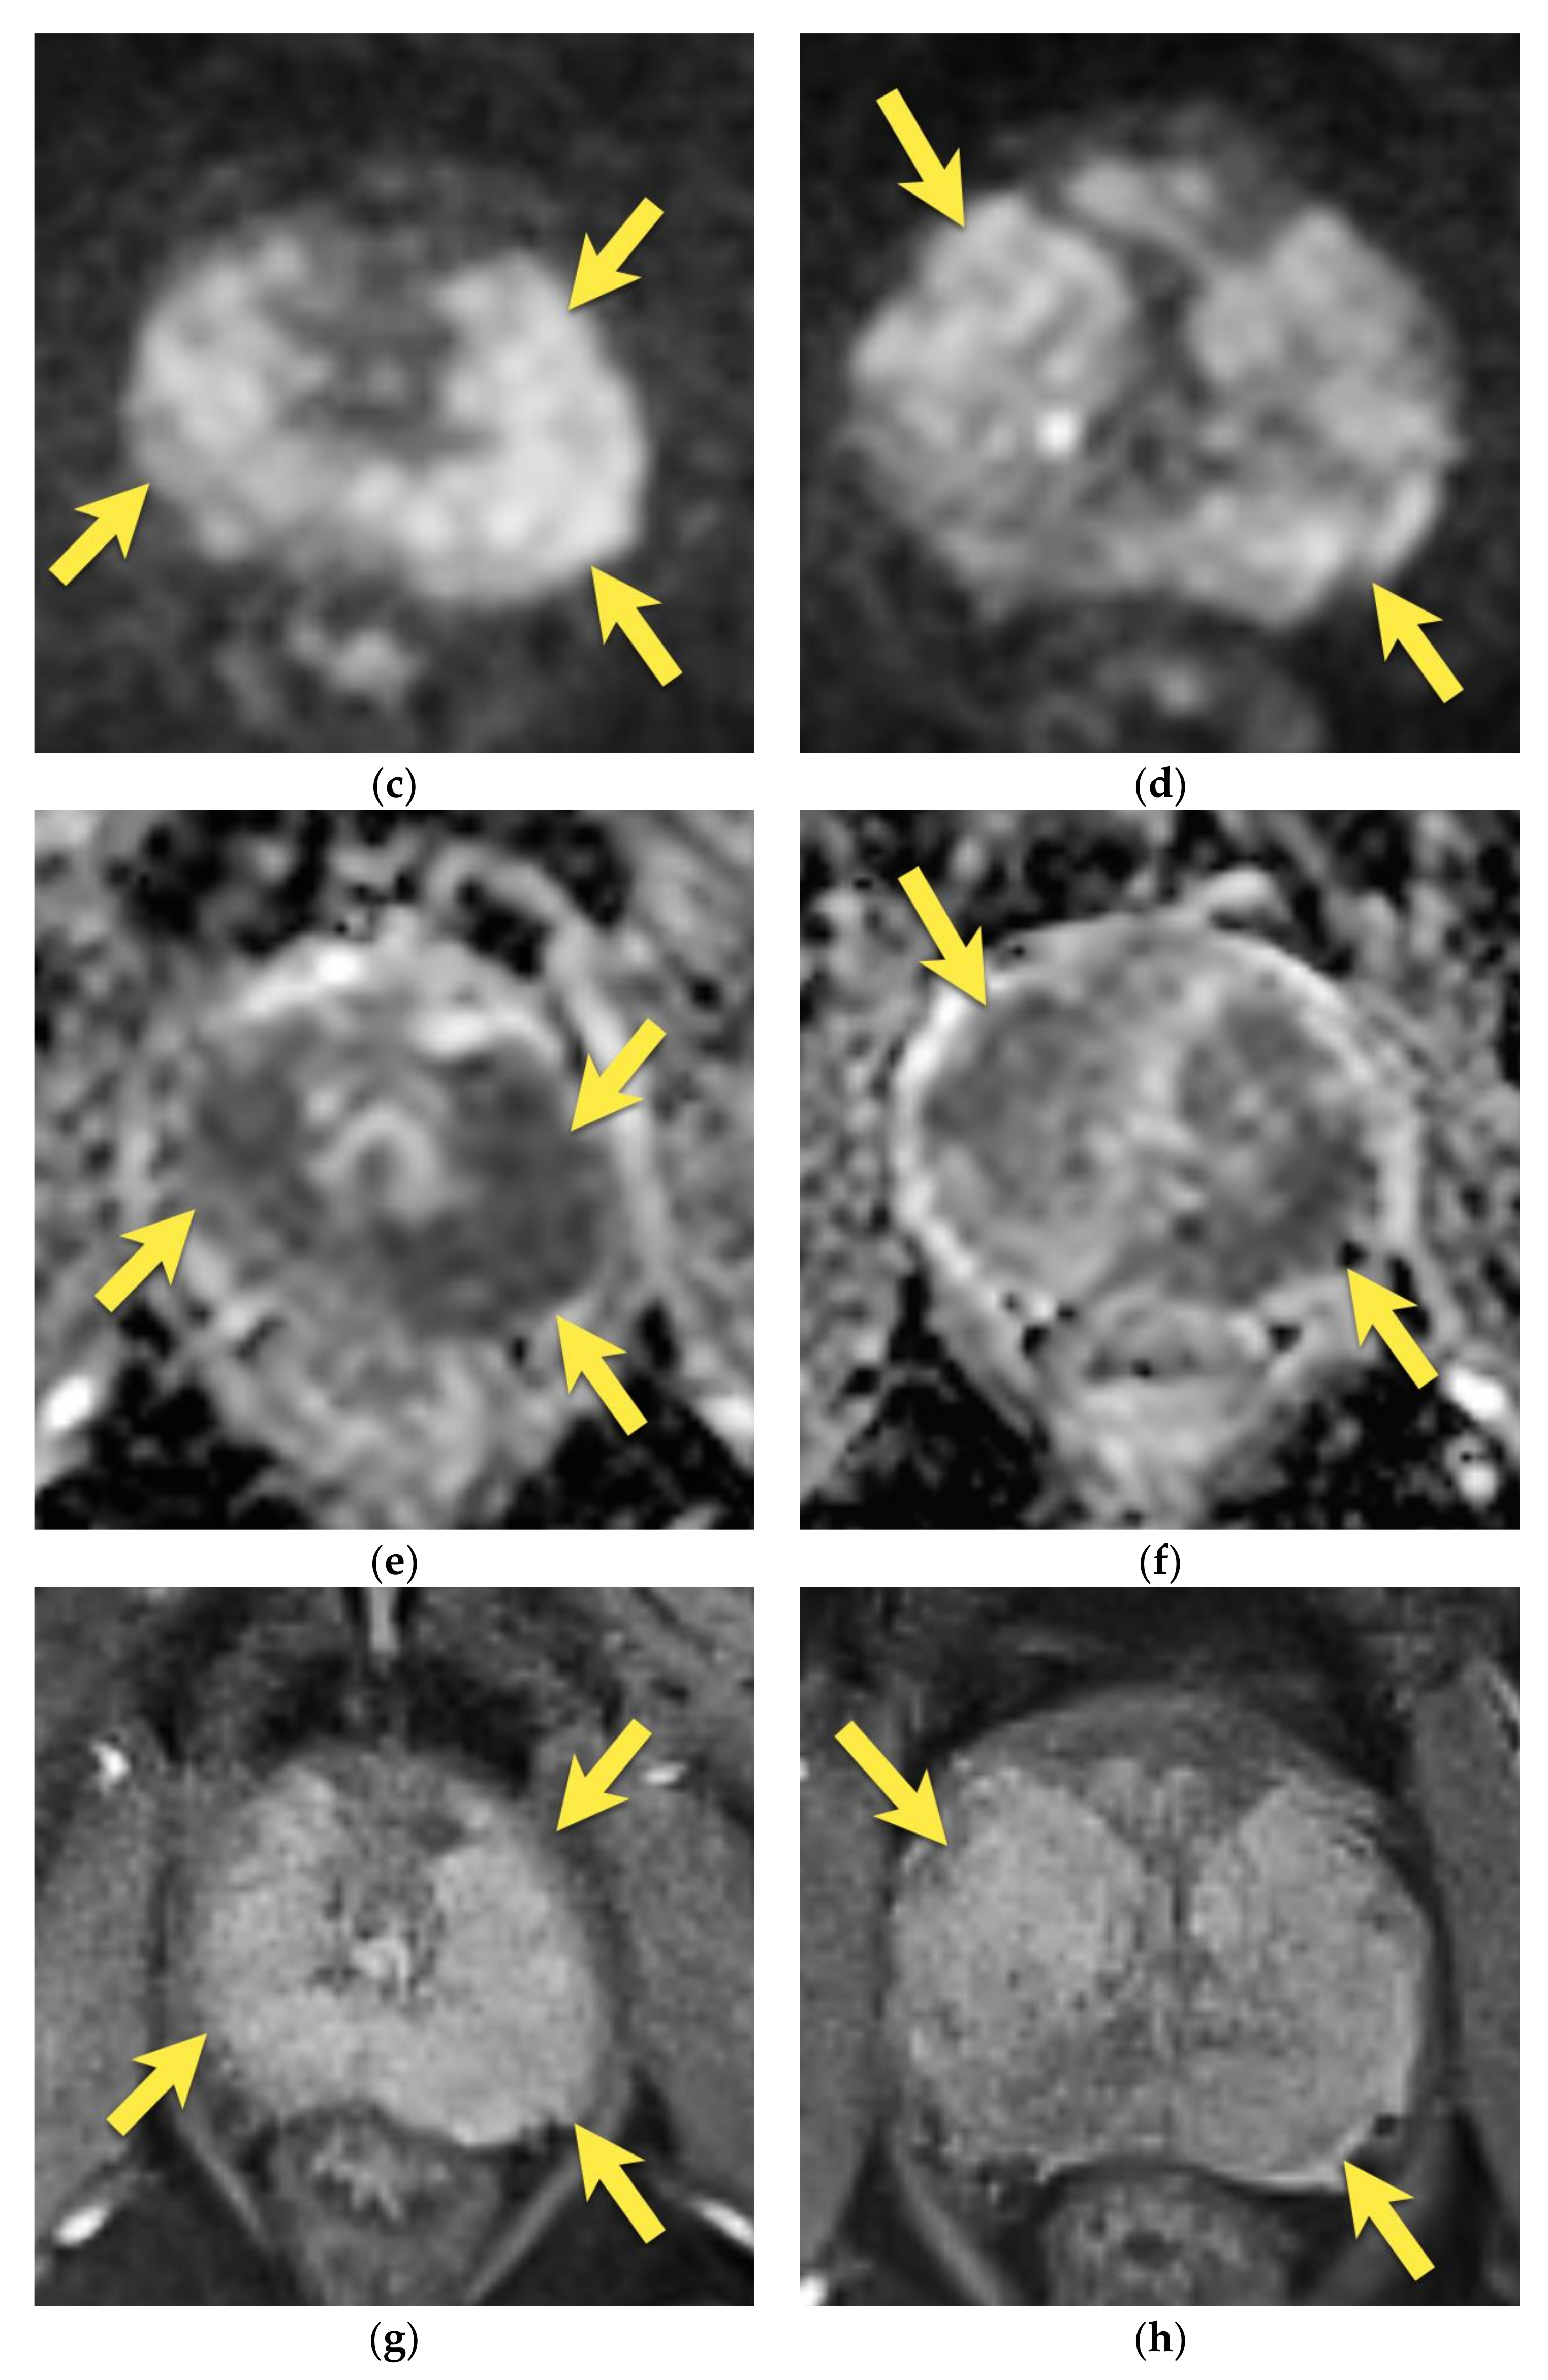

10. Prostatic Abscess

11. Quality of Images